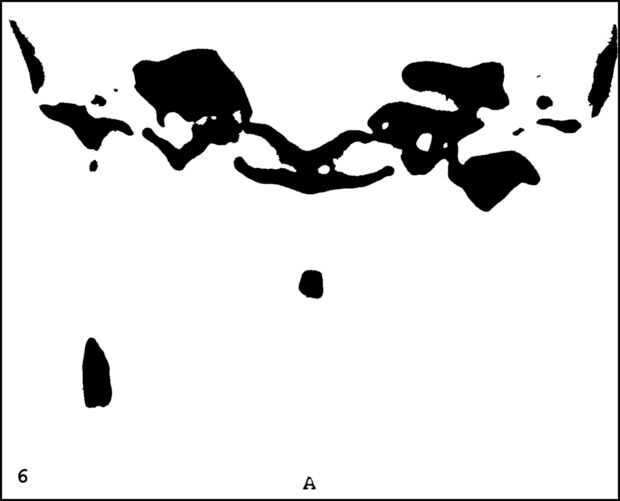

¡ Wow! Este fue por menos de 12 horas y tengo 1.000 visitas! Esto es sólo mi segundo instructable, así que estoy encantada. Decidí seguir adelante y publicar las imágenes que utiliza. Se trata de MRI de mi esposa, así que ella sólo puede tener lo mundos primer código abierto jefe. Mi lámpara utiliza solamente las primeras 16 capas, pero te di todos 34 que representa. Seguir adelante y usar estas imágenes, pero si lo haces, por favor me manden una imagen de lo que te ocurrió así que puedo hacerla sentir un poco famoso. ¡Que te diviertas!